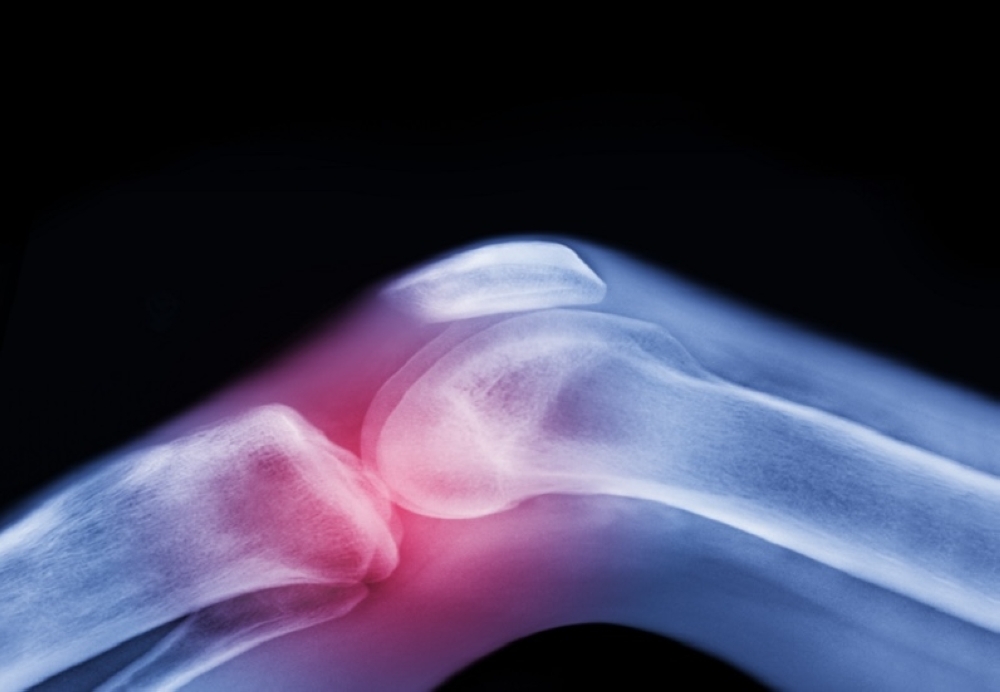

أجرى فريق من الباحثين في جامعة موناش دراسة جديدة تستهدف تأثير الميتفورمين، وهو دواء شائع لعلاج السكري من النوع الثاني، على الأشخاص الذين يعانون من التهاب مفاصل الركبة وزيادة الوزن أو السمنة.

وأظهرت النتائج أن الميتفورمين يمكن أن يساعد في تخفيف آلام الركبة الناتجة عن هشاشة العظام، مما قد يسهم في تأجيل الحاجة لعمليات استبدال الركبة.